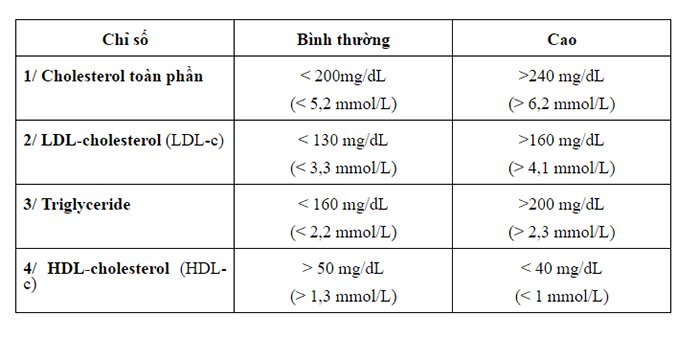

► Mỡ máu bao nhiêu là cao?

Xét nghiệm mỡ máu (blood lipid test) là xét nghiệm quan trọng đối với những cá nhân có nguy cơ mắc bệnh tim mạch cao chủ yếu nhằm kiểm tra nồng độ cholesterol và triglyceride trong máu. Mẫu máu thường được lấy vào buổi sáng, lúc đói (khoảng 3ml máu). Thường thì khi xét nghiệm mỡ máu, anh cần quan tâm đến 4 chỉ số:

Chỉ số cho biết mở máu cao hay không cao

Theo các bác sĩ cho biết, thông thường chỉ số cholesterol toàn phần lớn hơn 200mg/dL và chỉ số LDL lớn hơn 100mg/dL được xem là mo mau cao, nếu các chỉ số trên của bạn dưới những con số trên thì căn bệnh này vẫn chưa xảy ra với bạn. Nhưng một lần kiểm tra chưa chắc chắn là sau này bạn sẽ không mắc bệnh, các chỉ số này rất dễ thay đổi nếu bạn có một lối sống thiếu khoa học, theo lời khuyên của bác sĩ bạn nên đi kiểm tra các chỉ số này định kì. Để đảm bảo các chỉ số này ở mức ổn định và không tăng cao bạn cần ăn uống một cách hợp lý, cung cấp cho cơ thể những dưỡng chất cần thiết và hạn chế sử dụng các thực phẩm không tốt cho sức khỏe, sử dụng đa dạng các thực phẩm, tăng cường cung cấp chất xơ để trung hòa chất béo dư thừa bên trong cơ thể.